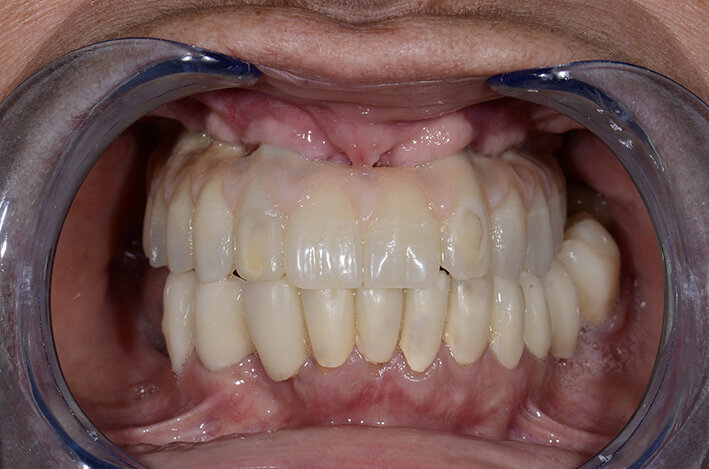

Il provvisorio immediato così funzionalizzato creerà un condizionamento ideale dei tessuti (Figg. 47-49) che porterà alla realizzazione del lavoro definitivo con la serenità di aver creato le condizioni per un successo a lungo termine del trattamento. L’immagine dei tessuti a tre mesi dal posizionamento implantare evidenzia i buoni auspici per un mantenimento a lungo termine degli impianti (Fig. 50).